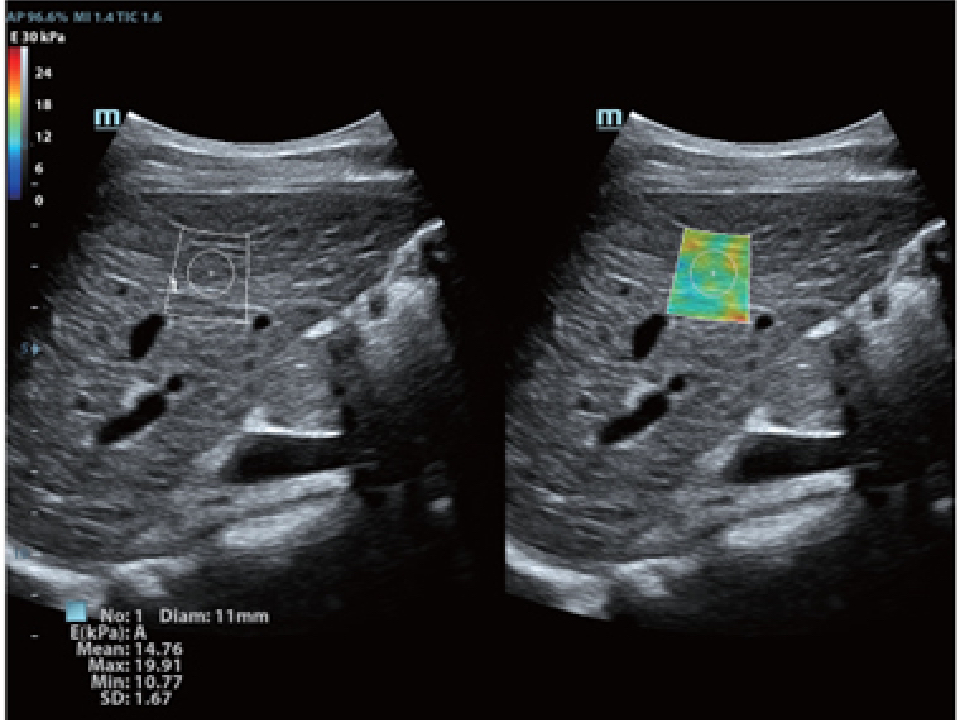

eXceptional Intelligence

Intelligence throughout entire workflow

Intelligence integrated in professional diagnostic tools for whole examination procedures,DC-80 with X-Insight provides exceptional intelligence integrated in professional diagnostic tools across wide applications and throughout whole examination procedures, from regular screening to further diagnosis and clinical follow up.